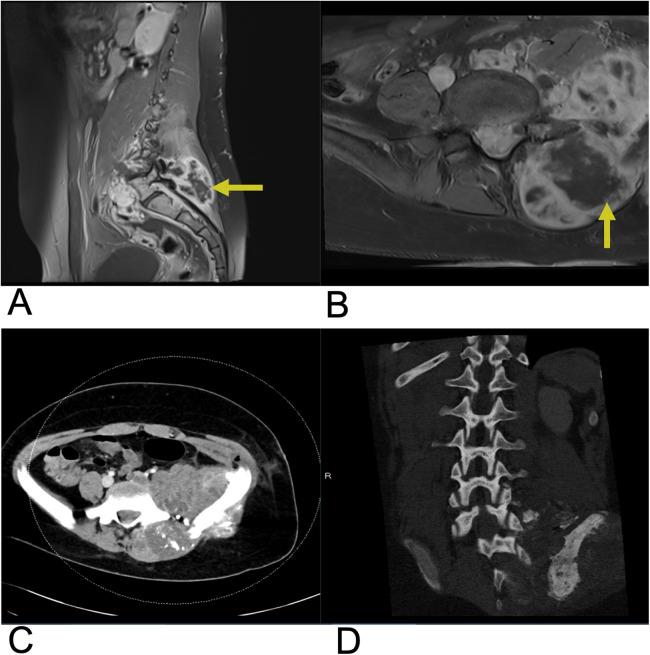

Spinal lesions encompass a diverse range of pathologies, including primary and secondary tumors, infectious processes, vascular malformations, traumatic injuries, and degenerative conditions, each with distinct imaging characteristics crucial for accurate diagnosis and management. Imaging plays vital roles in assessing lesion morphology, anatomical localization, and neurological impact, guiding clinical decision-making and therapeutic planning. This review systematically explores spinal lesions based on their anatomical compartments, highlighting key radiological features and providing a comprehensive reference for radiologists.

脊柱病变包括多种病理情况,包括原发性和继发性肿瘤、感染性病变、血管畸形、创伤性损伤以及退行性疾病,每种病变都具有独特的影像学特征,这些特征对于准确诊断和治疗至关重要。影像学在评估病变形态、解剖定位和神经影响方面发挥着至关重要的作用,指导临床决策和治疗规划。本综述基于解剖分区系统地探讨脊柱病变,突出关键的放射学特征,并为放射科医生提供全面的参考。